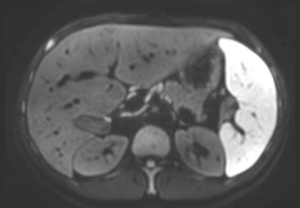

SmartSpeed は、空間分解能を最大 65% 向上させることができます¹。これにより、画像診断の精度を向上させるための情報を提供できます。

AI ベースの Philips SmartSpeed 再構成は、高速化技術の新たなベンチマークとなっています。この技術により Compressed SENSE があらゆる面で向上し、優れた画質と診断精度を維持しながらスキャン時間を短縮できます。"

Philips SmartSpeed には優れたノイズ除去機能が搭載されており、スキャン時間を延長することなく、非常に高分解能のイメージングを実現できます。これは、血管系の小さな病変を描出する場合などに非常に重要です。"